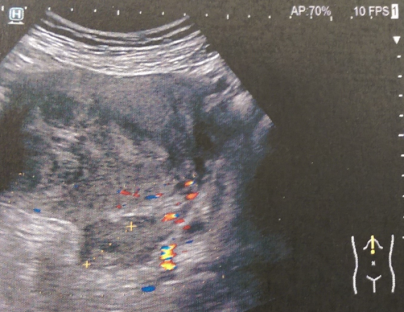

Κλασική υπερηχογραφική εικόνα εντύλιξης λεπτού εντέρου (Ευγενική παραχώρηση Dr. V. Penopoulos)